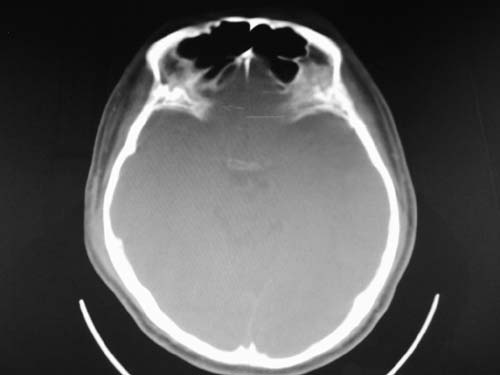

脑中线内血肿,是硬膜下的吗?

脑中线内血肿——硬膜下血肿。

脑中线内血肿——硬膜下血肿。我们一般认为中线即可是硬膜下,也可是蛛网膜下腔的。边缘锐利,张力高的考虑硬膜下的,边缘模糊的,考虑下腔的。如果有老师有肯定的答案,麻烦下给我发个短信

硬膜下血肿,有颅骨骨折

支持镰旁硬膜下血肿,颅骨骨折,头皮损伤.

这个病人年龄不小吧,右侧脑沟不清,中线结构稍有左移,右侧额颞顶及右镰旁硬膜下血肿,另有蛛血,骨折。

外伤后引起的颅骨骨折、硬膜下血肿、皮下血肿,颅骨骨折引起的矢状窦破裂,形成大脑纵裂内血肿。